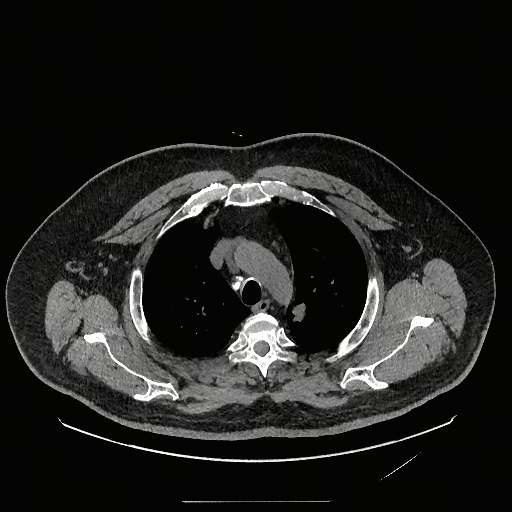

Medical grounding reasoning takes a raw image, reasons through what it observes, and outputs bounding boxes marking the abnormalities. This isn't simply helpful visualization. It's the mechanism by which reasoning becomes verifiable. Another clinician can look at the marked region and independently judge whether the finding exists.

Medical grounding reasoning marks abnormalities with bounding boxes, making diagnostic conclusions traceable and independently verifiable.

Similarly, magnification-assisted reasoning mimics how radiologists actually work. When something appears ambiguous at normal magnification, you zoom in. The model learns this as a taught skill. When uncertain about a finding, it doesn't speculate. It calls a zoom tool, examines the magnified region, and then reasons about what it observes.

Magnification-assisted reasoning shows the model analyzing an original image, calling a zoom tool to examine suspicious areas, and rendering conclusions based on the magnified view.

These capabilities matter because they bridge the gap between "the model gave an answer" and "I understand why and can verify it." Without grounding and magnification, even correct diagnoses feel like black boxes. With them, the reasoning becomes transparent and subject to clinical judgment.